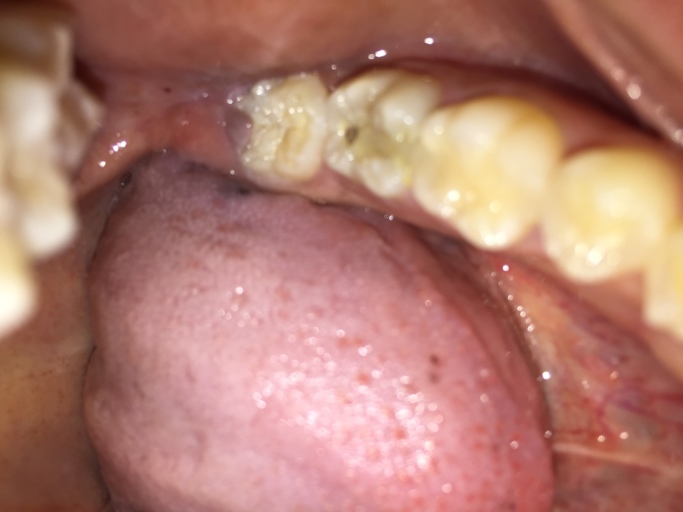

Why are my teeth falling apart despite good brushing?

I just got my braces off two weeks ago and my teeth have become so horrible since then. I brushed my teeth 1-2 times a day (I know it's not that great) throughout my time with braces (3.5 years) and when I first got them off I had like huge white spots on the top of my teeth, a little discoloration, and a HUGE cavity on my front tooth. I brushed my teeth enough for this not to happen! For the past two weeks, I have brushed by teeth 3-4 times a day for 1-2 minutes and flossed constantly, and since then my teeth have gotten 10x worse. My cavity has gotten much worse, I have TWO new ones on my front teeth (one on top and one on bottom) and on the white spots from lack of fluoride it is legitimately orange and has bands of brown despite me brushing CONSTANTLY. On one of the cavities I literally watched as pieces of tooth came off when brushing (what???) I'm literally close to tears because my parents spent close to $10,000 on braces just to have my teeth be destroyed. What is happening! And my mom won't take me to a dentist because it is not covered under insurance (totally ridiculous but oh well can't persuade my mom). Any actual help or explanation is appreciated! Thanks :)